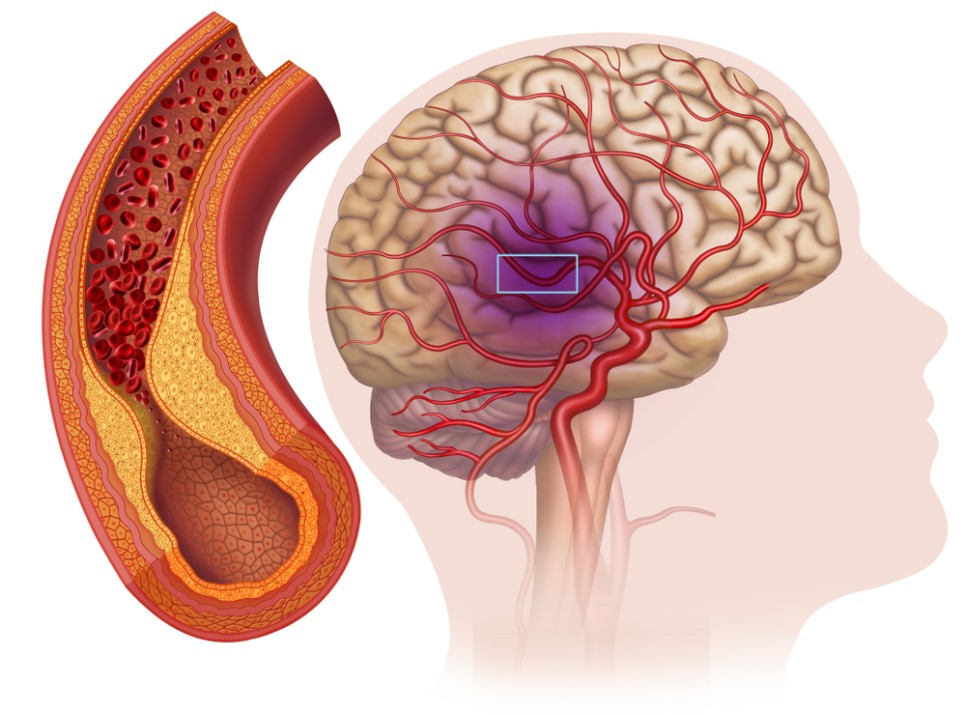

하지만 경동맥이 60% 이상 막혀 어지럼증, 감각이상, 안면신경마비, 언어장애, 반신부전마비가 나타나는데 그때서야 아는 게 많습니다.

뇌로 혈관이 막힌 경우 뇌경색으로 인한 뇌기능 마비, 심하면 사망할 수도 있습니다.경동맥 협착증 치료